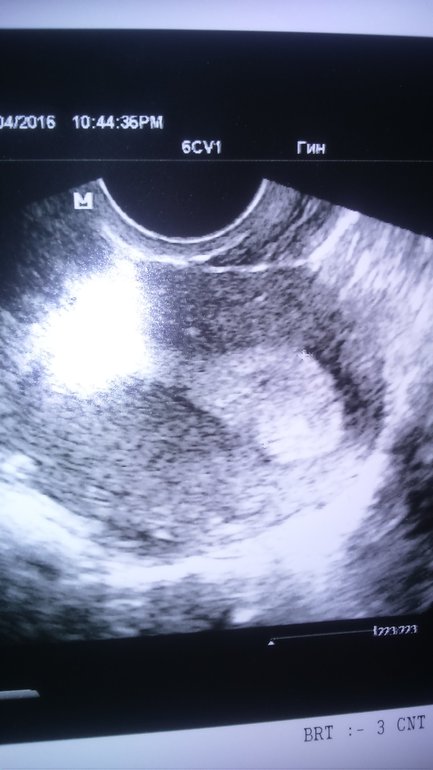

какой срок у вас? а по узи разве не сказали ничего?

Пока ещё нет, просто сказали затемненный участок и всё,к врачу только на следующей недели

а тесты делали? рано еще на таких сроках узи делать, на 6 неделе можете еще увидеть что то....даже услышать)))но не ранее))))

ну тогда порядок другой нужен, чем на узи сразу...если думали на Б, то для начала тест- потом хГЧ если положительный вдруг, а потом узи УЗИ, чтобы подтвердить маточную Б

Ну если ту точку считать ПЯ, то есть... а какой срок то? Тесты что говорят?? Если +, то ждите ещё.

У меня тоже так было... но оказалось не оно, к сожалению.